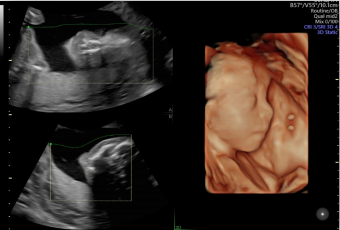

智能NT和智能IT

胎兒頸后透明層/顱內(nèi)透明層標(biāo)準(zhǔn)化測量,減少主觀因素差異。